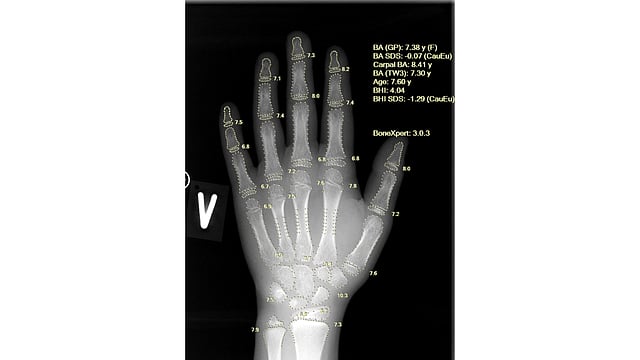

Using a single left-hand X-ray, BoneXpert provides a comprehensive, multi-method assessment that includes Greulich-Pyle (GP) bone age, Tanner-Whitehouse (TW2/TW3) bone age, carpal bone age, Bone Age Standard Deviation Score (SDS) and Bone Health Index (BHI). This depth of analysis supports early identification of constitutional growth delay and endocrine abnormalities, enabling timely clinical intervention.